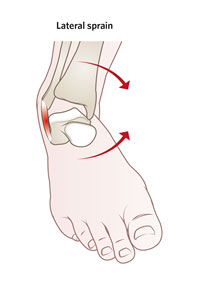

常見的足踝扭傷(拗柴)情況,例如在不平坦的路面上行走或跑步、走路時踩空或者穿著不合適的鞋子(例如: 高跟鞋),都很容易導致踝關節內翻或外翻扭傷,通常是內翻扭傷(±95% ),外翻扭傷較少 (±5%)。

| 足踝內翻扭傷 |